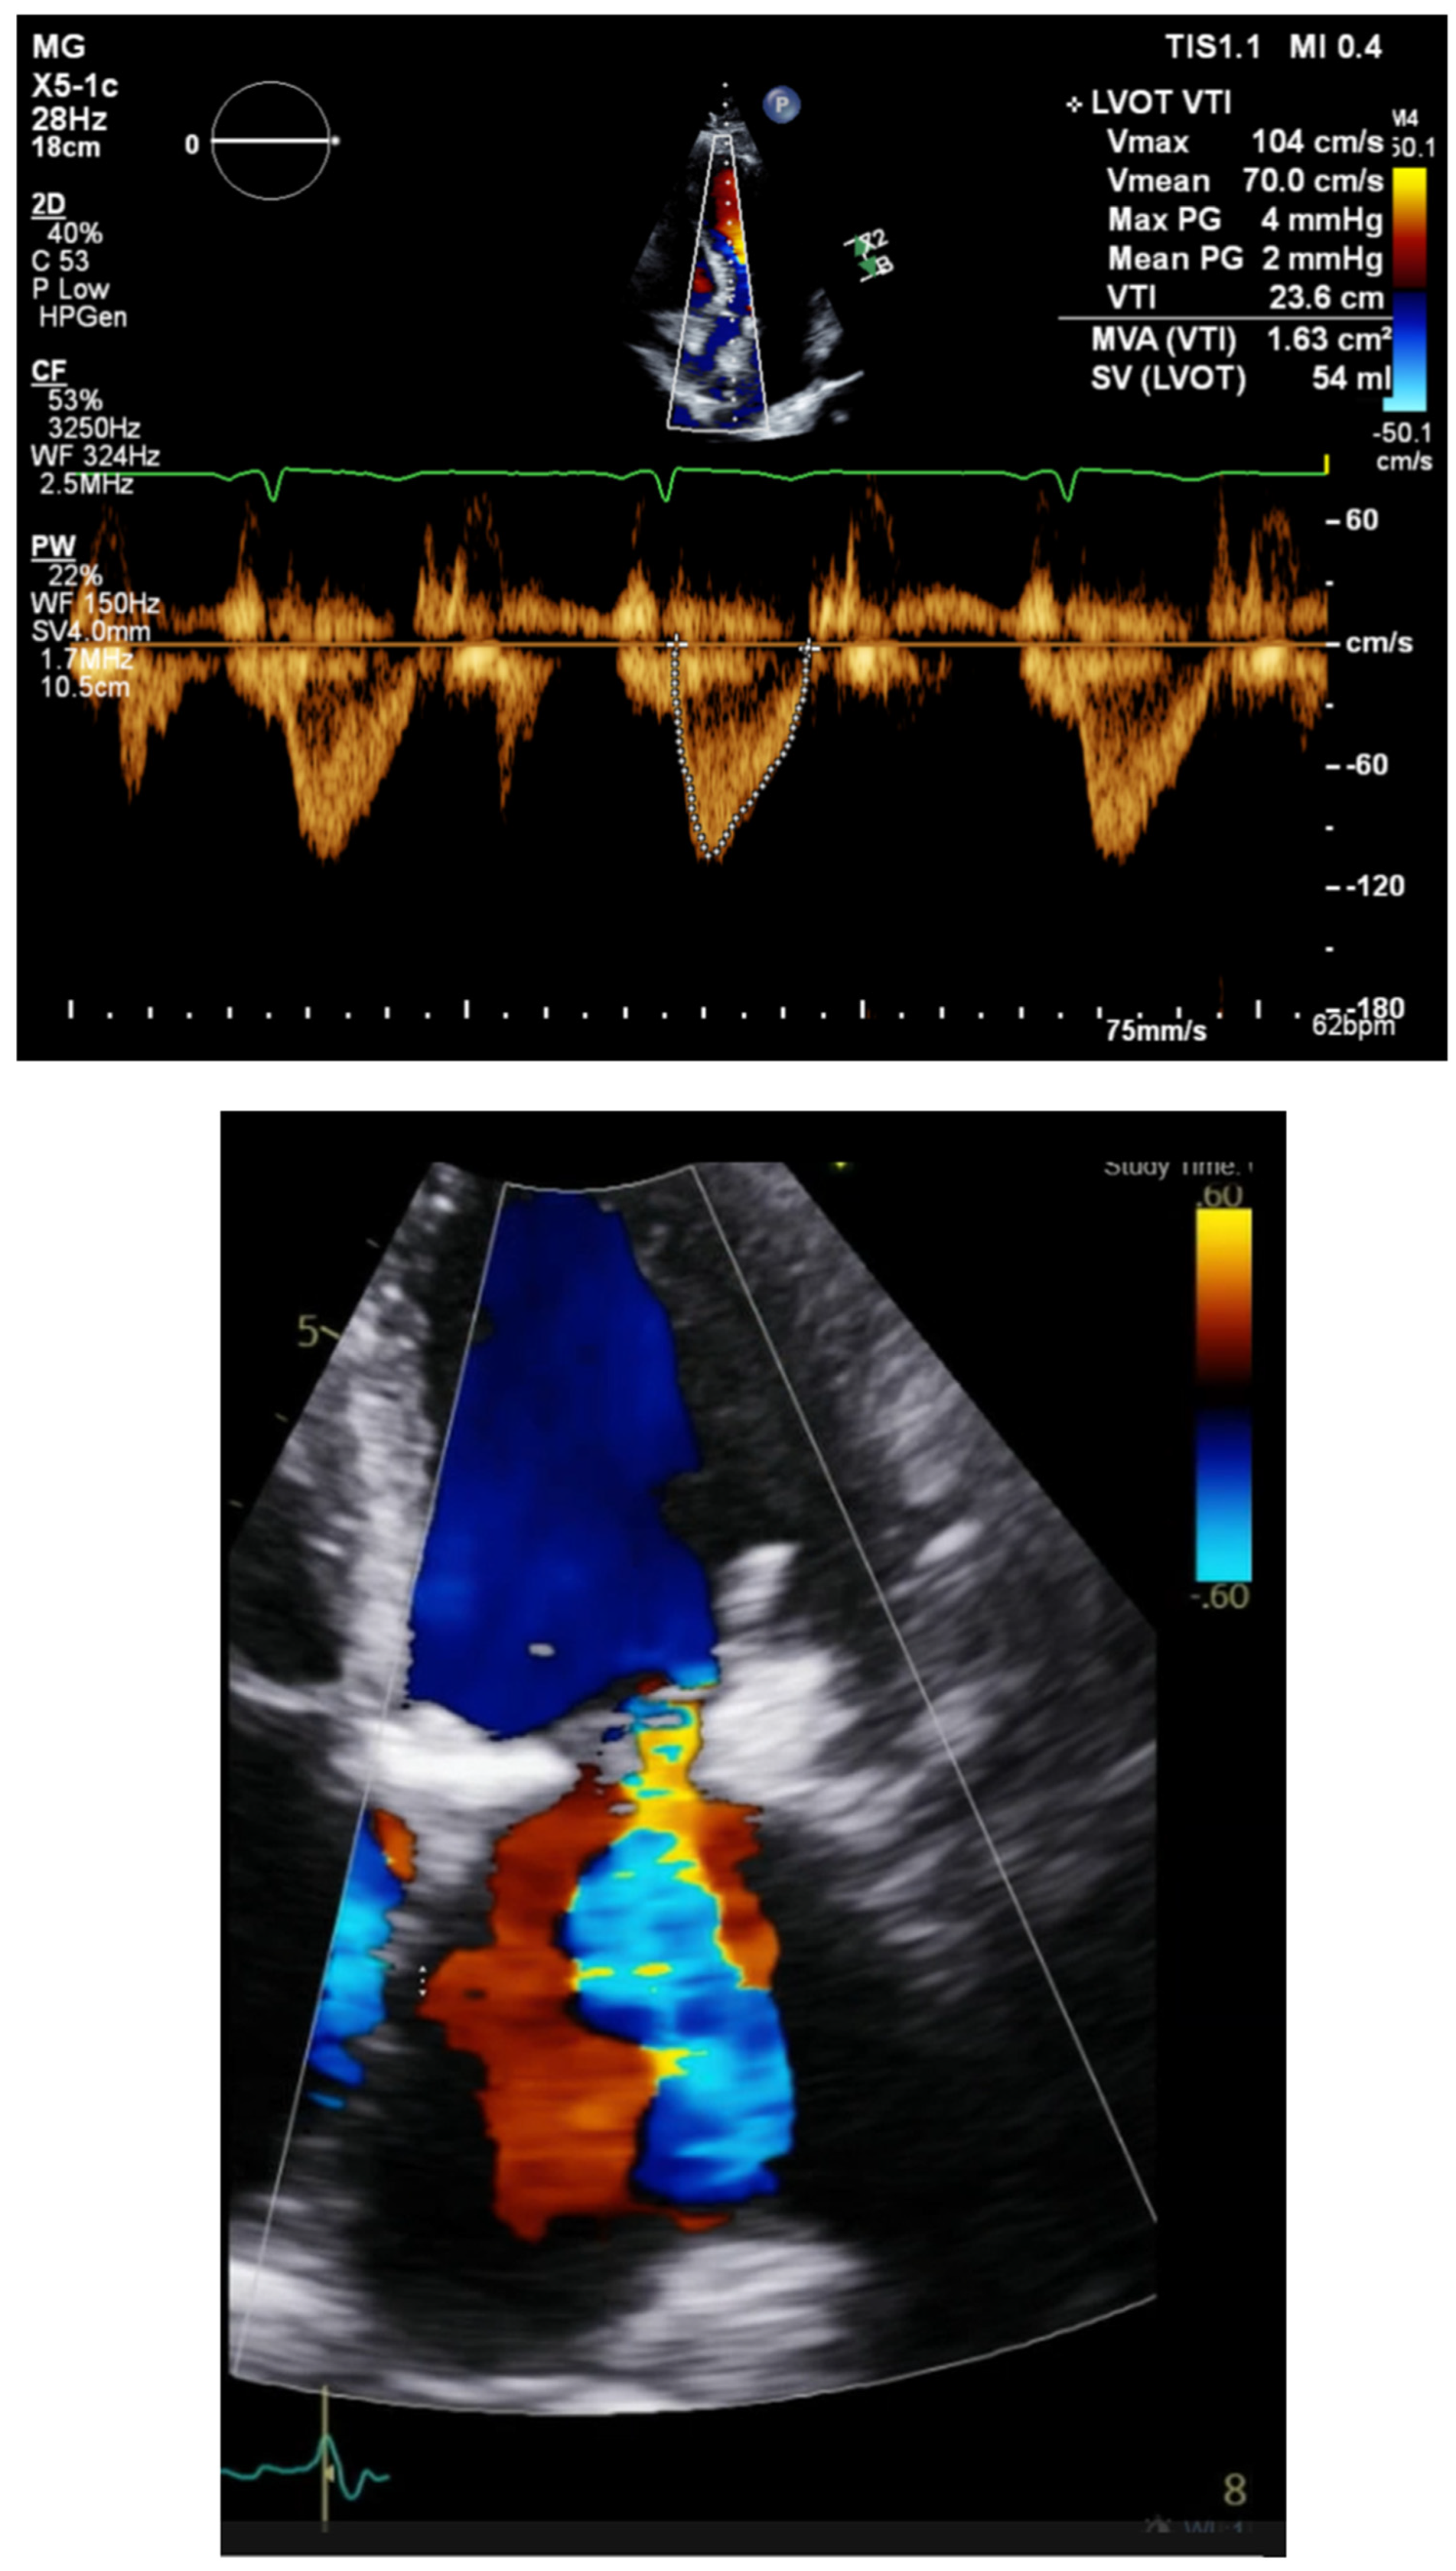

Step 3d Timing of the LV and RV goal is to decrease mitral regurgitation and increase the LVOT integral. Evaluate the LVOT integral and adjust LV/RV timing to maximize the LVOT integral and reduce mitral ERO. The RV LV timing delay is chosen by iteration of an interval to optimize LVOT VTI Figure 4.

Figure 4. LVOT integral and mitral regurgitation ERO.